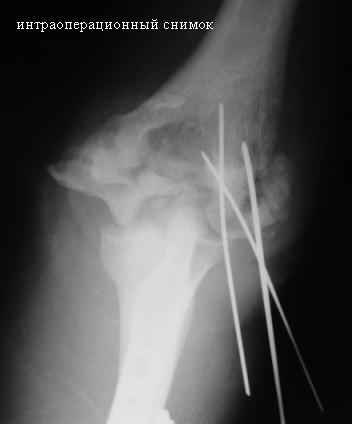

Стойкая комбинированная контрактура правого локтевого сустава

Увжаемые коллеги! На консультации больной со стойкой комбинированной контрактурой правого локтевого сустава.

В прошлом - спортсмен, сейчас охранник. Травма 2 августа 2008г., автодорожная. Оперирован в одной из больниц города. Остеосинтез, два месяца гипс. Объем движений с тех пор не изменился. Боли после физнагрузки (пытается тренироваться).

Имеется ложный сустав мыщелка плечевой кости.

Необходимо выполнить остеосинтез и добится сращения и только потом возможен-артролиз локтевого сустава.

Случай интересный. Но для решения поставленных Вами вопросов необходимо ответить на несколько вопросов. Имеется ли консолидация диафизов локтевой и лучевой костей? Действительно ли имеется ложный сустав мыщелка плечевой кости? Насколько дисконгруэнтны суставные поверхности? Желательно провести спиральную компьютерную томографию с 3D реконструкцией. Если локтевая и лучевая кости сросшиеся, то на вскидку, как кажется необходимо провести стабильный погружной остеосинтез мыщелка и одновременный артролиз сустава из 2-х боковых доступов. Иммобилизация только на несколько дней для уменьшения болевого синдрома.